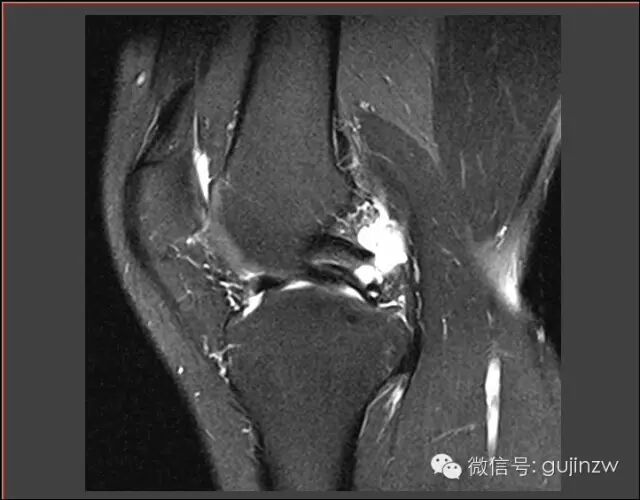

病例3

• 男,25岁。

• 主诉:打篮球扭伤致右膝关节疼痛半年。

• 症状:轻微跛行,右膝关节疼痛,活动时有不稳感,无交锁、打软腿。

• 体征:膝关节活动度:0-135度,浮髌试验弱阴性,内外侧关节间隙无压痛。

• 被动挤压:麦氏征(-),Apley征(-)。

• 主动挤压:Ege‘s征(-),Thessaly  20°征(+)。